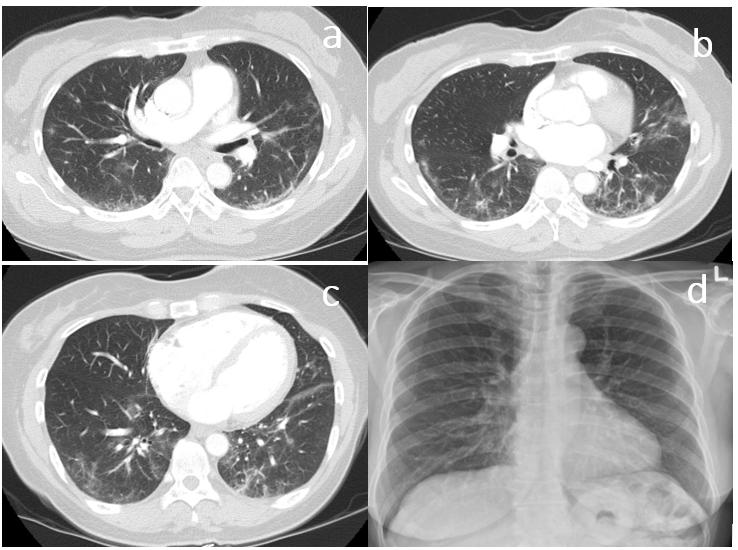

Figure 6 (a) Initial chest X-ray during COVID infection shows multifocal bilaterl dense airspace disease. (b-c-d) different cuts of axial CT-Chest shows bilateral subpleural reticulation.